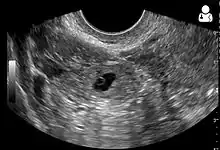

Transvaginal ultrasonography

An ultrasound showing a gestational sac with fetal heart in the fallopian tube has a very high specificity of ectopic pregnancy. It involves a long, thin transducer, covered with the conducting gel and a plastic/latex sheath and inserted into the vagina.[32] Transvaginal ultrasonography has a sensitivity of at least 90% for ectopic pregnancy.[5] The diagnostic ultrasonographic finding in ectopic pregnancy is an adnexal mass that moves separately from the ovary. In around 60% of cases, it is an inhomogeneous or a noncystic adnexal mass sometimes known as the "blob sign". It is generally spherical, but a more tubular appearance may be seen in case of hematosalpinx. This sign has been estimated to have a sensitivity of 84% and specificity of 99% in diagnosing ectopic pregnancy.[5] In the study estimating these values, the blob sign had a positive predictive value of 96% and a negative predictive value of 95%.[5] The visualization of an empty extrauterine gestational sac is sometimes known as the "bagel sign", and is present in around 20% of cases.[5] In another 20% of cases, there is visualization of a gestational sac containing a yolk sac or an embryo.[5] Ectopic pregnancies where there is visualization of cardiac activity are sometimes termed "viable ectopic".[5]

A pregnancy not in the uterus[33]

The combination of a positive pregnancy test and the presence of what appears to be a normal intrauterine pregnancy does not exclude an ectopic pregnancy, since there may be either a heterotopic pregnancy or a "pseudosac", which is a collection of within the endometrial cavity that may be seen in up to 20% of women.[5]

A small amount of anechogenic-free fluid in the recto-uterine pouch is commonly found in both intrauterine and ectopic pregnancies.[5] The presence of echogenic fluid is estimated at between 28 and 56% of women with an ectopic pregnancy, and strongly indicates the presence of hemoperitoneum.[5] However, it does not necessarily result from tubal rupture but is commonly a result from leakage from the distal tubal opening.[5] As a rule of thumb, the finding of free fluid is significant if it reaches the fundus or is present in the vesico-uterine pouch.[5] A further marker of serious intra-abdominal bleeding is the presence of fluid in the hepatorenal recess of the subhepatic space.[5]